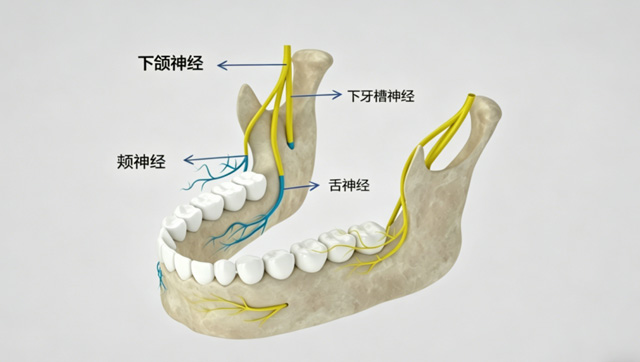

由于解剖差异,有些人的下牙牙根离下牙槽神经很近,拔牙时如果操作不当,可能损伤到该神经。

下牙槽神经是一个感觉神经,没有支配面部表情的功能,它受损后会出现麻木症状,但不会造成面瘫。面神经属于混合神经,大部分为支配表情肌运动的运动神经,我们打麻药和拔牙的操作都是在口内进行的,不会涉及面部区域,因此也不会损伤到面神经。

拔牙手术的第一个步骤是麻醉,常用的麻醉方式包括:表面麻醉、浸润麻醉、神经阻滞麻醉几类。医生需要熟悉口腔颌面部的解剖结构,并具有一定的临床经验,才能精准把握进针位置、深度、麻醉剂量和注射时间,这些因素都会影响到麻醉效果。

为什么有些人拔牙后会出现嘴歪、嘴麻、闭不上嘴、说话不利索等情况呢?

这应该和麻醉有关。当注射麻药时进针比较深,药物透过面部软组织扩散到了相关神经的位置,形成了暂时性的相关肌肉麻痹,可能会出现类似“面瘫”的症状。但这是一过性的,等麻药药效消失后会自行恢复。

比如,在患者常规注射位点有一些病变的情况下,注射时有可能为了避开这些病变而麻药注射过深,就可能造成唇部肌肉暂时性的麻痹,形成一过性的嘴歪。